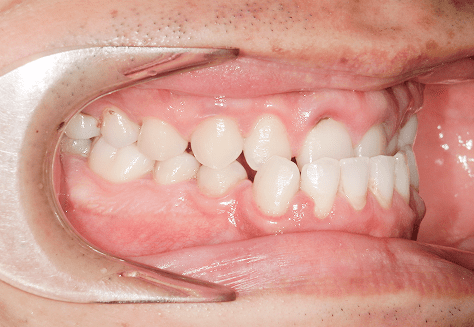

M.U

治療前

治療後

主訴

下の歯が特にガタガタなのが気になる。上の前歯が1本反対になっている。

診断

下顎前突・叢生・反対咬合

年齢/性別

20代/男性

抜歯部位

非抜歯

使用装置

上下インビザライン(PBM使用)

保定装置

ビベラリテーナー

料金

初回資料採得・・・・・・・30,000円

診断料・・・・・・・・・・33,000円

動的治療終了時資料採得・・5,500円 -

基本料金

950,000円

診察料金

5,500円×16回

治療期間

1年7カ月